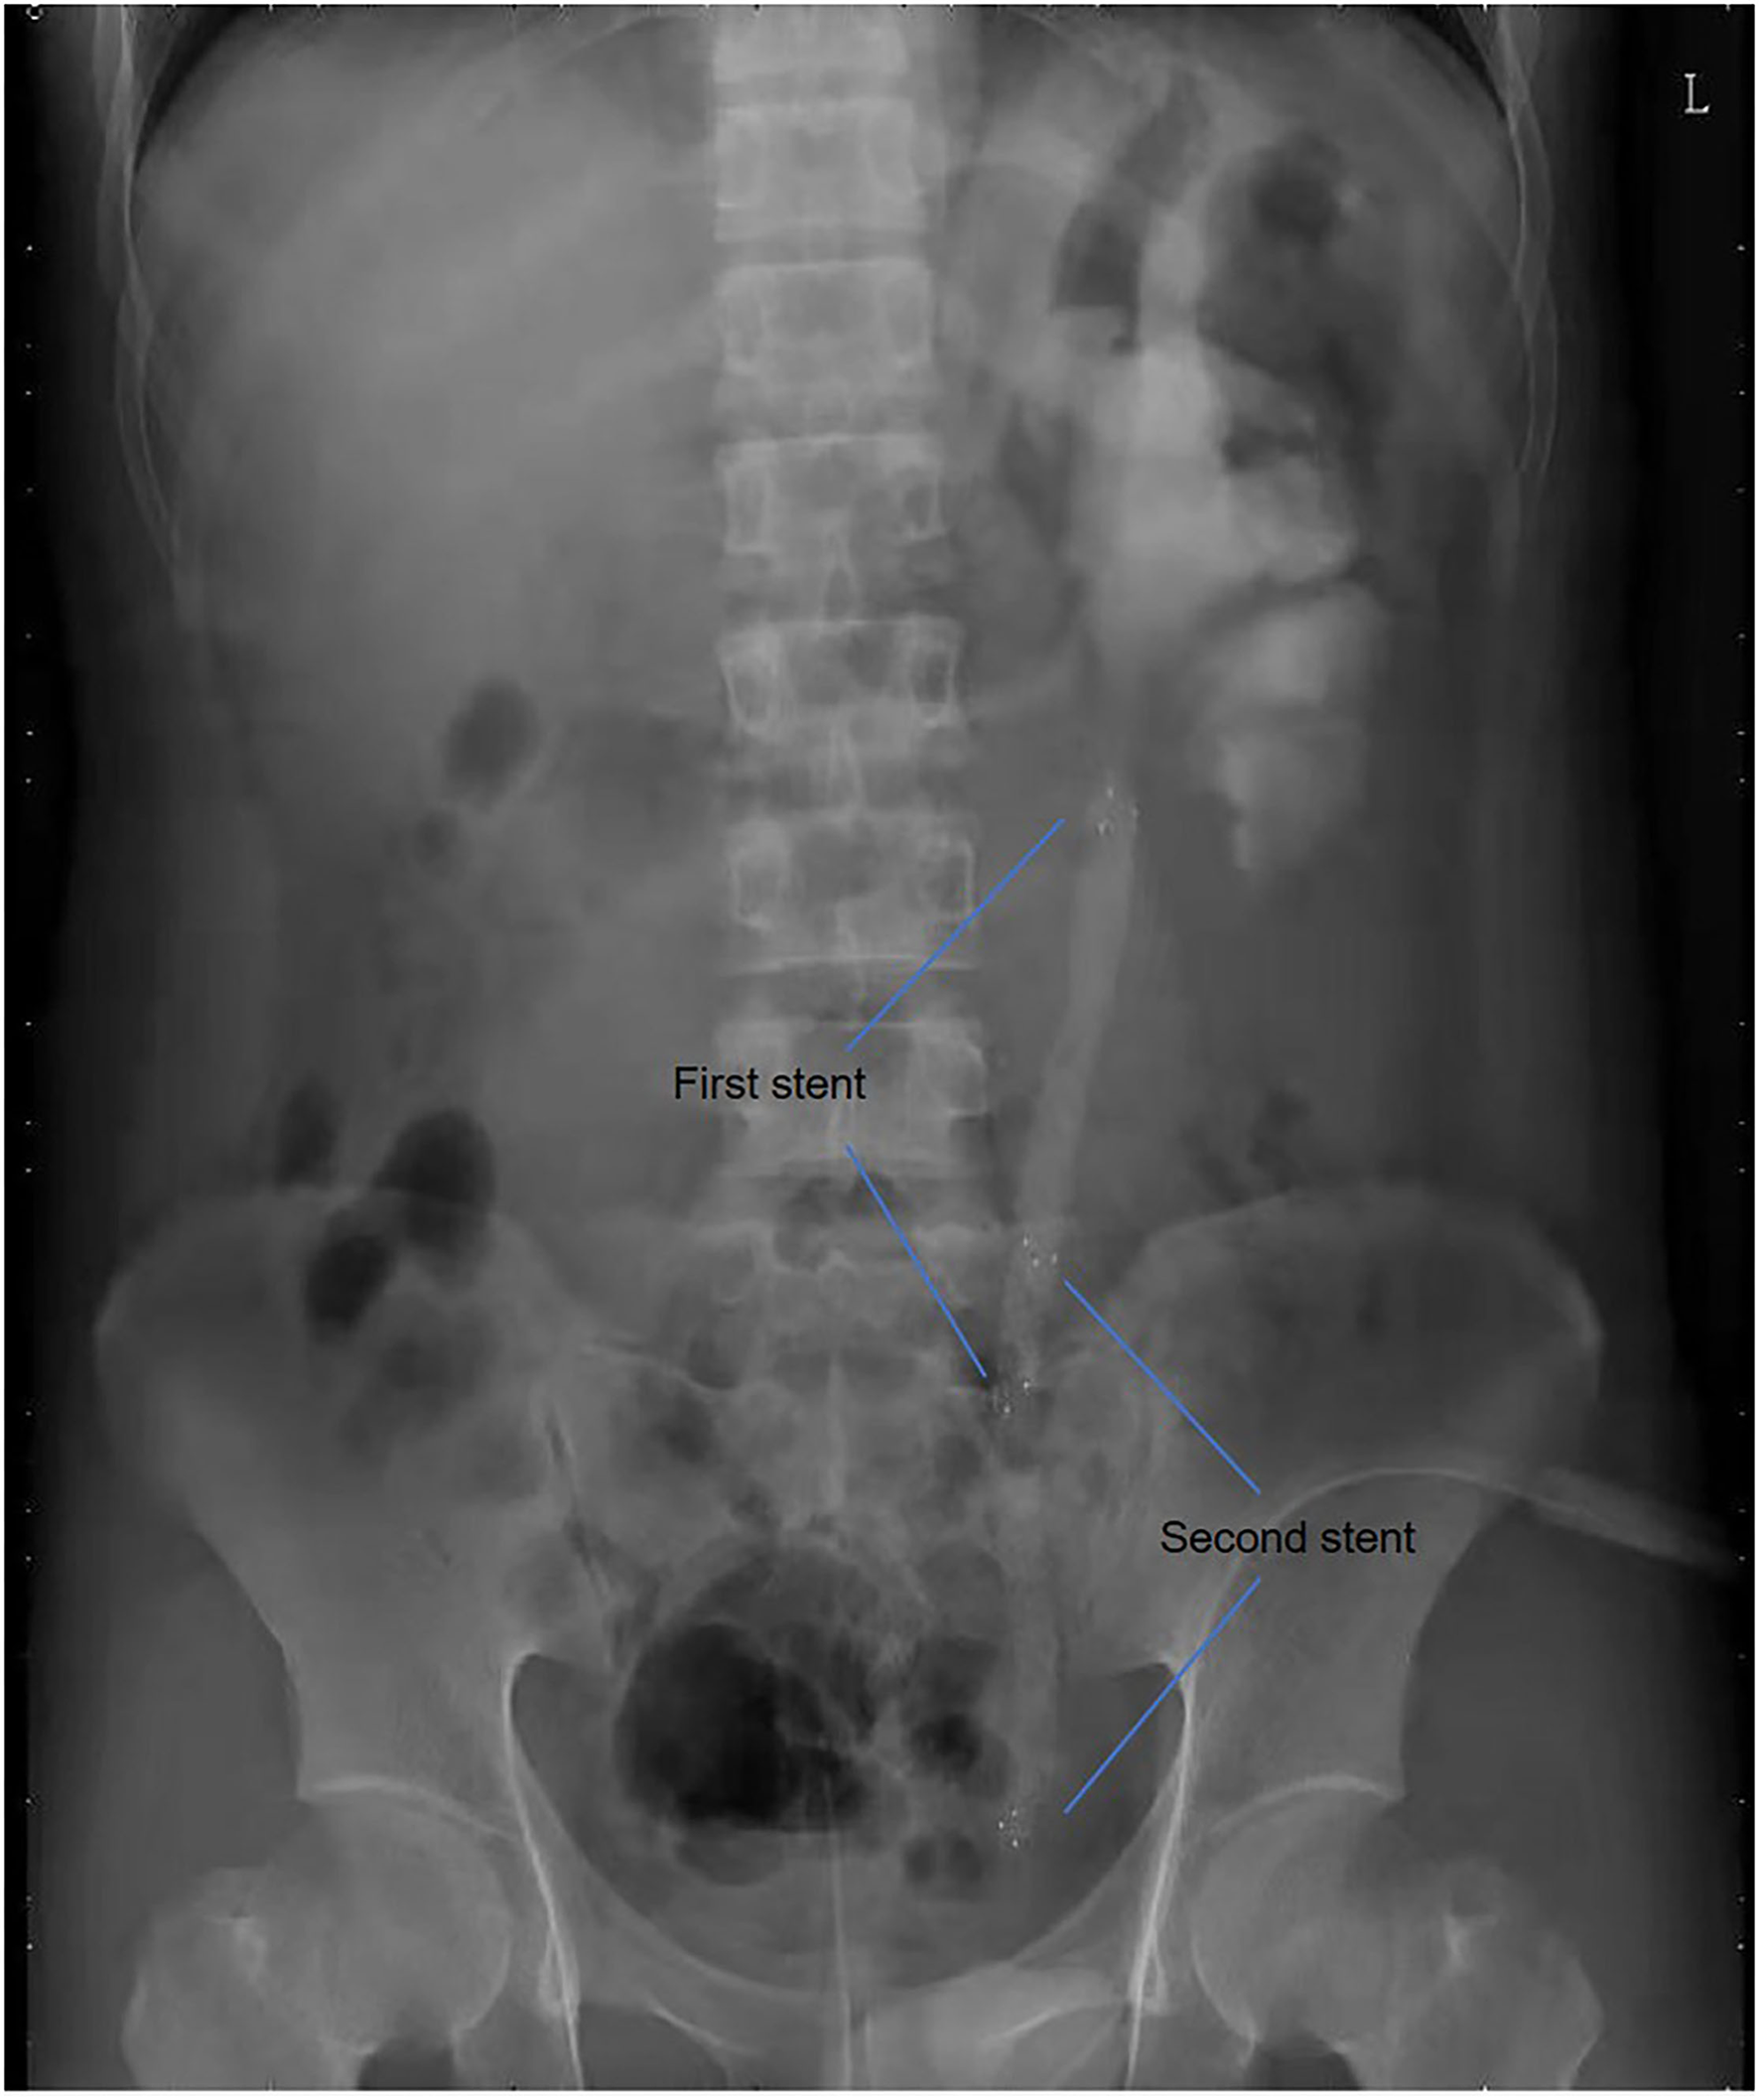

All operations were performed by the same endourological skilled surgeon. The surgical procedures were similarly to our previously reported (10, 11). The position and length of ureteral stricture are determined by retrograde or antegrade ureterogram (Figure 1). The two Allium Stents, 10 and 12 cm, are currently available in our hospital. Different stents were selected according to the length of the ureteral strictures. All ureteral strictures were diluted by 18 F or 21 F balloon before the MUS was retrogradely implanted. After confirming that the narrowed segment was dilated satisfactorily, a 24 F or 30 F-coated metal ureteral stent was inserted. We initially implanted one stent for proximal ureteric stricture, and found that the stents migration rate was as high as 80% (Figure 2). So, we improved the surgical technique and inserted two stents in tandem for proximal ureteral strictures and long strictures (Figure 3). When the stent was released satisfactorily, radiography was performed again to confirm the stent position and patency. The migration stents were endoscopically adjusted to the normal position or exchanged as we previous reported (11).

Figure 3

Two stents in tandem for proximal ureteric strictures and long strictures.

In our study, 58.3% of patients have suffered failed pyeloplasty. Secondary surgical ureteroplasty for recurrent ureteral strictures may be technically difficult and associated with considerable morbidity. In fact, after pyeloplasty, the renal pelvis usually tortuous and thick. In this case, it is easy to cause stent migration if only one metal stent is implanted. Therefore, we implanted double tandem stents for 18 selected patients.